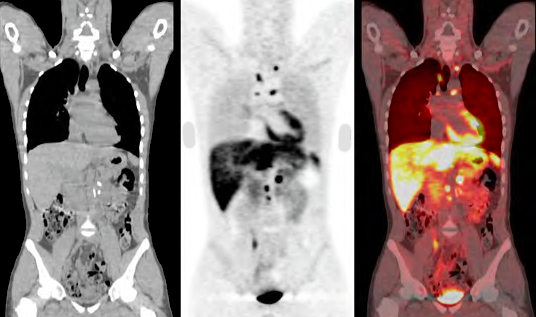

5. ET SCAN

6. Detección de metástasis de cáncer de próstata